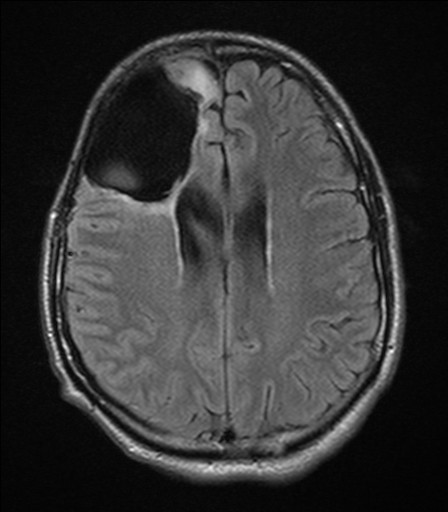

Magnetic Resonance Imaging Of Malignant Or Benign. Secondary ...

MaGneTIc Resonance IMaGInG of BRaIn TuMoR CEwebsource.com PAGE OF 1 ExPirES July 15, 013 BRaIn TuMoR MR IMaGInG Primary malignant brain tumors, such as gliomas, ... Access Content

Robust Classification Of Primary Brain Tumor In MRI Images ...

Robust Classification of Primary Brain Tumor in MRI Images using Wavelet as the cell phones, or chemicals similar to formaldehyde and vinyl chloride. Symptoms of brain tumors incorporate continual headache, nausea and vomiting, eyesight, ... Retrieve Document